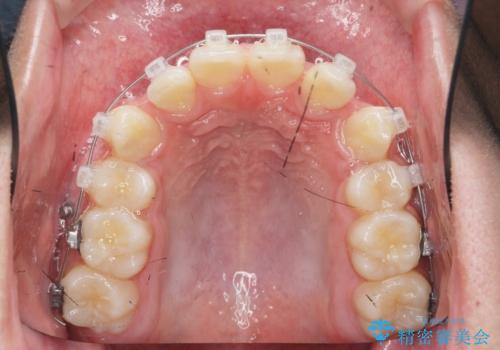

- 前歯のがたつきが原因で歯ブラシしづらい、見た目を改善したい!と矯正治療を希望され来院されました。

スペースの不足が見られるため、小臼歯の4本抜歯を行いマルチブラケットを用いた矯正治療を計画します。

噛み締めが強く、治療に時間がかかりましたが矯正治療の仕上がりに満足いただくことができました。